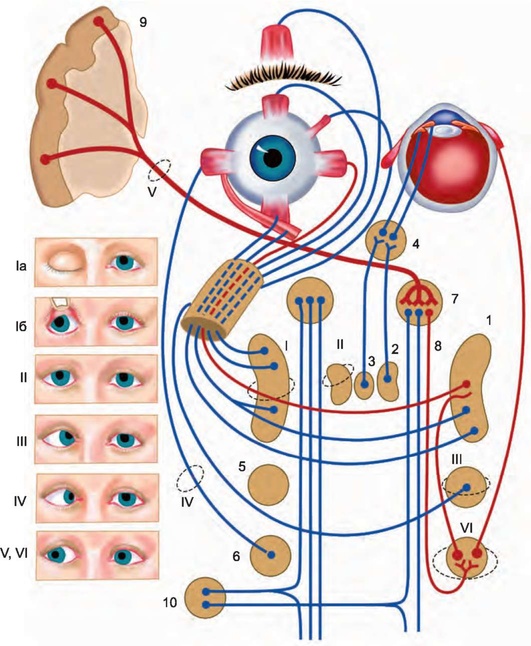

Рис. 5.1. Иннервационная взаимосвязь мышц глаза: 1 - мышцы, суживающие и расширяющие зрачок; 2 - ресничный узел; 3 - ядро глазодвигательного нерва; 4 - основное ядро III нерва; 5 - ядро IV нерва; мостовой центр взора; 6 - ядро VI нерва; 7 - корковый центр взора; 8 - парасимпатическое ядро III нерва; 9 - нижняя прямая мышца; 10 - наружная прямая мышца; 11 - верхняя прямая мышца; 12 - мышца, поднимающая верхнее веко; 13 - нижняя косая мышца

Рис. 5.6. Иннервация глазных мышц и медиальные продольные пучки, обеспечивающие их связи между собой и с другими структурами мозга: 1 - ядро глазодвигательного нерва; 2 - добавочное ядро глазодвигательного нерва (ядро Якубовича-Эдингера-Вестфаля); 3 - заднее центральное ядро глазодвигательного нерва (ядро Перлиа); 4 - ресничный узел; 5 - ядро блокового нерва; 6 - ядро отводящего нерва; 7 - собственное ядро медиального продольного пучка (ядро Даркшевича); 8 - медиальный продольный пучок; 9 - адверсивный центр премоторной зоны коры большого мозга; 10 - латеральное вестибулярное ядро. Синдромы поражения: Ia и Iб - крупноклеточного ядра глазодвигательного (III) нерва; II - добавочного ядра глазодвигательного нерва; III - ядра IV нерва; IV - ядра VI нерва; V и VI - поражение правого адверсивного поля или левого мостового центра взора. Красным цветом обозначены пути, обеспечиващие содружественные движения глаз